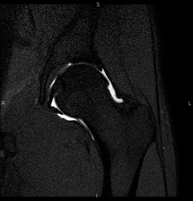

- Hip MRI

Examination for the study of injuries to tendons, muscles and hip joints. Enables early detection of hip osteoarthritis. It is very useful for detecting bursitis and dynamic osteopathy of the pubis, which is common in athletes. It lasts approximately 20 minutes. It is a radiation-free procedure.

- Hip MRI arthrography

Examination to study injuries to small anatomical structures of the joint that are commonly injured in patients suffering from dislocation or impingement (narrowing space). Prior to the examination, a contrast fluid is injected into the joint, guided by X-ray imaging. The total duration of the two procedures is 50 minutes.